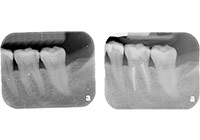

齲齒由口腔中多種因素復合作用所導致的牙齒硬組織進行性病損,表現為無機質脫礦和有機質分解,隨病程發展而從色澤改變到形成實質性病損的演變過程。齲齒是細菌性疾病,因此它可以繼發牙髓炎和根尖周炎,甚至能引起牙槽骨和頜骨炎癥。(圖01~04)

圖4